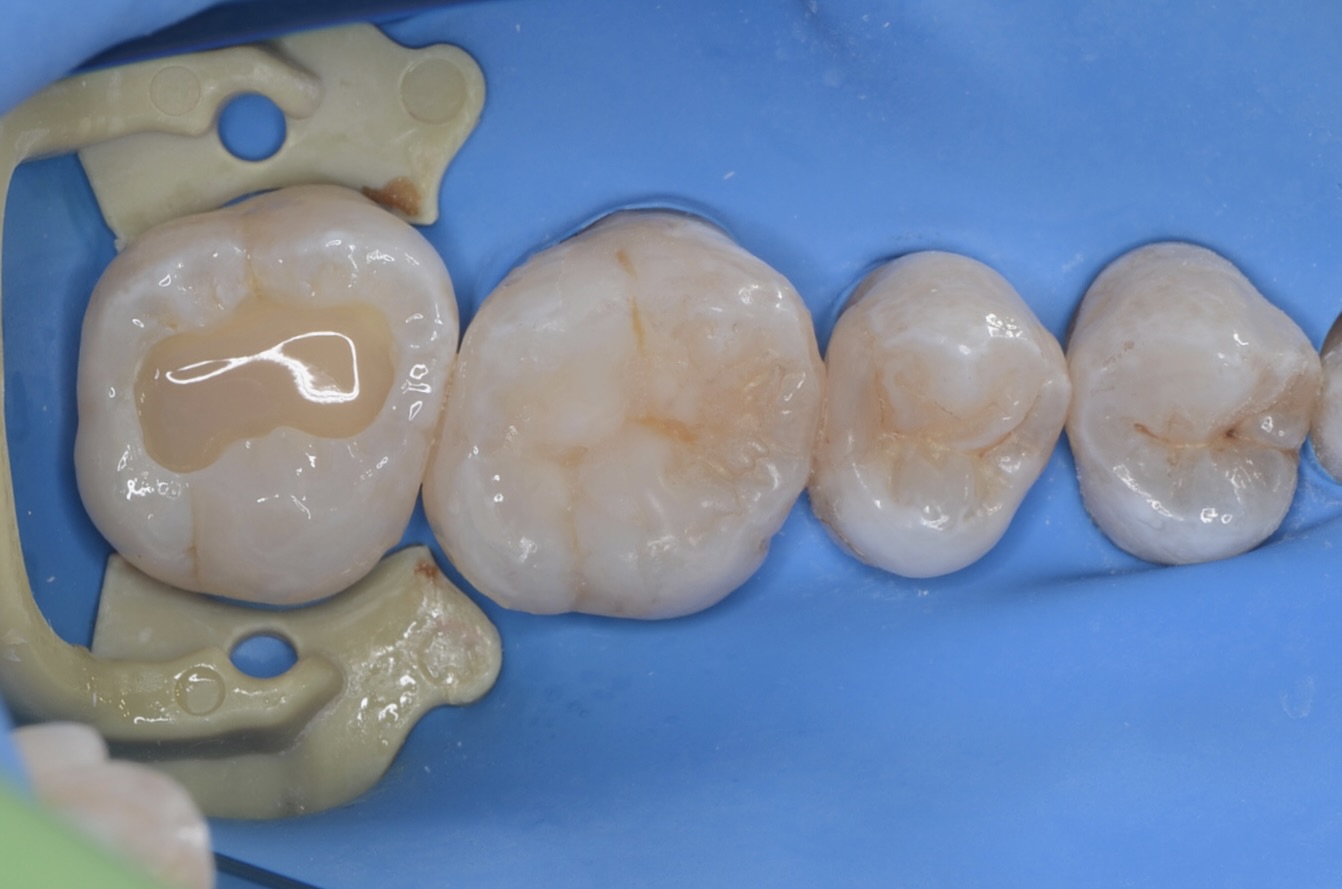

ラバーダム装着

7番のインレーを外します。 -

インレー

インレーの下の虫歯を除去します。 -

知覚過敏抑制材

虫歯を削った後は、知覚過敏抑制材を刷り込みます。 -

ダイレクトボンディング

象牙質の範囲まで、濃い目の色のレジンを充填します。中の色を濃くしておくと、最終的に僅かに透けて立体感が出ます。 -

充填完了

天然歯の形態を模倣して滑らかに仕上げました。 -